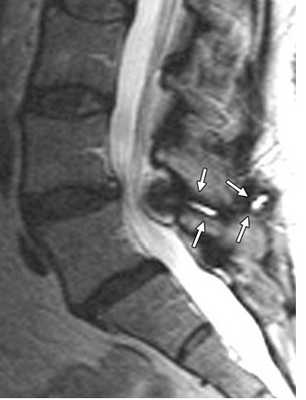

(Слева) Сагиттальная МР-томограмма в режиме Т1, пациент после вентрального спондилодеза СЗ-С5 с костной пластикой. Признаки дегенеративных изменений С5-С6 сегмента с развитием на этом уровне центрального стеноза позвоночника. Врожденный костный блок на уровне С6-С7 еще более увеличивает биомеханические перегрузки на уровне С5-С6 сегмента.

(Справа) Сагиттальная МР-томограмма этого же пациента в режиме Т2. На уровне С5-С6 видны признаки дегенерации и центрального стеноза с сужением субарахноидального пространства. Зона гиперинтенсивности паренхимы спинного мозга на уровне С5-С6 представляет собой очаг миеломаляции.